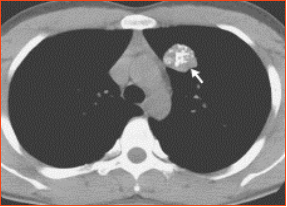

肺结节按性质分为良性结节和恶性结节。常见的良性结节有炎症、结核瘤、错构瘤、肺内淋巴结、血管瘤等。恶性结节有原发性肺癌和转移瘤等。还有一些是癌前病变,比如非典型性腺瘤样增生,这些癌前病变随着病变的进展,可发展为肺癌。据统计,结节越大恶性概率越大。

典型的错构瘤(内有爆米花样钙化)